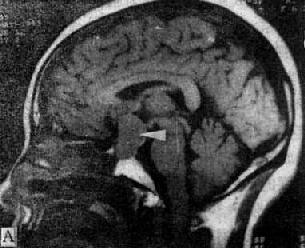

MRI因无骨骼伪影干扰,且有多维扫描断面和多种参数成像的优点,适宜于鞍区(图5-1-6A、B)和颅底特别是后颅凹病变的观察;应用血管的流空效应不用造影剂即可显示肿瘤与周围血和宾关系和供血情况。Gd-DTPA的应用可早期发现微小听神经瘤、垂体微腺瘤以及肿瘤的脑膜侵犯。MRI对钙化病变的显示不如CT敏感。

MRI 适宜于观察CT扫描为等密度的亚急性脑内血肿,已如前述。脑梗塞的发现MRI比CT扫描要早,一般起病后6小时MRI即可出现异常。脑干和小脑腔隙性梗塞灶的探测,MRI明显优于CT。脑梗塞灶在T1WI上呈低信号,在T2WI上呈高信号(图5-1-6C、D)。

图5-1-6 MRI扫描SE序列图像

在矢状面(A)和冠状面(B)T1WI可见垂体肿块向鞍上延伸,呈等信号区(→);在横断面T1WI(C)和T2WI(D)上分别可见左枕和右基底节区脑梗塞灶呈低和高信号区(→);在矢状面T1WI(E)和横断面T2WI(F)上,可见基底动脉瘤环形影,其内为低信号和高信号区,高信号区为瘤内血栓形成(→)